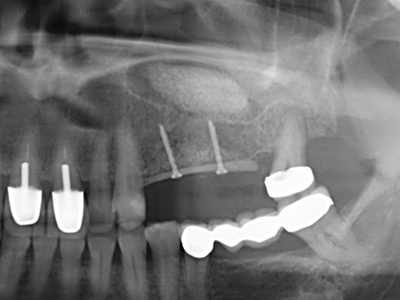

When surgical procedures are performed on bone in the immediate vicinity of sensitive structures such as blood vessels or nerves, rotary instruments pose a significant risk of iatrogenic injury. Piezoelectric devices can be helpful for preparation of bone covers and removal of hard tissue close to nerves, particularly for exposure of nerves after iatrogenic injury but also during nerve lateralization for resective and reconstructive procedures or implant placement (Fig. 17-20). Light contact between the piezotip and the nerve does not generally result in damage but proceeding incautiously with saw-like motions or attachments where a residual bone substrate remains may cause temporary or even permanent nerve damage. However, the risk of damage is considered to be substantially lower than when using saws or milling instruments (Pereira, Gealh et al. 2014).